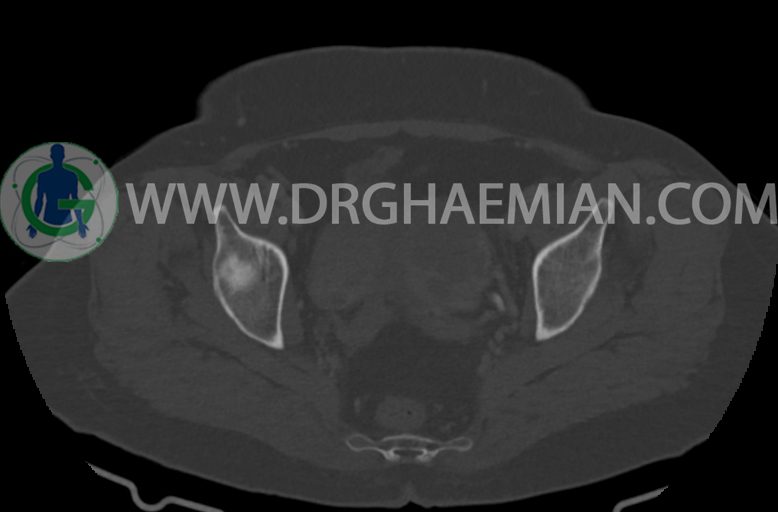

سی تی اسکن شکم و لگن با استفاده از اشعات ایکس تصاویر عرضی از ناحیه شکم و لگن ایجاد میکند. در این کیس موسینوس کیست آدنوما، شواهد هیسترکتومی، ضایعه در سمت راست لگن، کیست در کبد و … دیده می شود.

–شواهد هیسترکتومی

–تغییرات DJD در L5/S1

مشهود است.